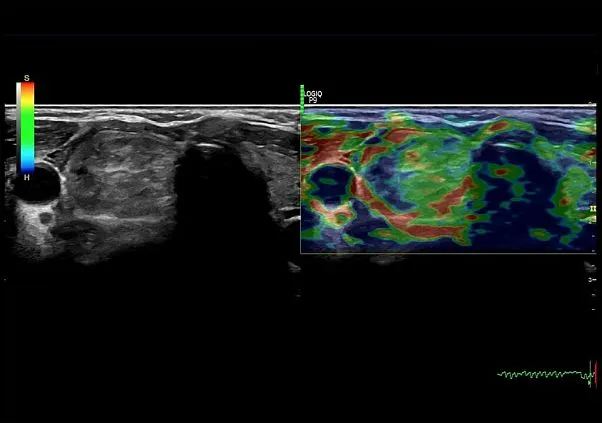

Клинические изображения

Благодаря технологии XDClear клинические изображения становятся более чёткими, с минимальным уровнем шумов и артефактов. Интеллектуальные алгоритмы обработки данных, поддержка мультичастотных датчиков и автоматические функции — такие как допплерография, 3D/4D-визуализация и автоматические измерения — позволяют проводить широкий спектр исследований с высокой точностью. Удобная панель управления, регулируемый монитор и компактные размеры делают использование аппарата максимально комфортным.

- DICOM опция.

- Elastography Imaging - режим эластографии. Поддерживается датчиками C1-5-RS, L6-12-RS, 12L-RS, 9L-RS, ML6-15-RS, L4-12t-RS, E8CS-RS, и BE9CS-RS.

- Q-analysis Option for Elastography and CF/PDI - программа количественного анализа для эластографии и анализа васкуляризации в режиме ЦДК и ЭД.

- Инновационные инструменты, в том числе недопплеровская визуализация кровотока в B-режиме (B-Flow), 3D/4D сканирование, эластография, стресс-эхокардиография, тканевая допплерография (TVI/TVD) и УЗИ с контрастным усилением (CEUS).